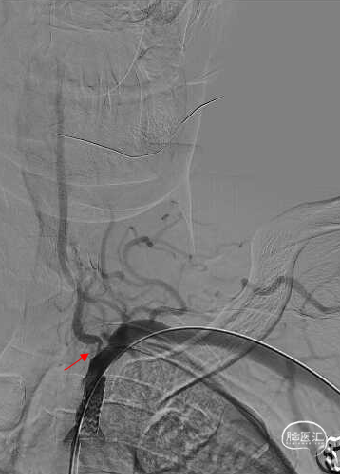

右侧椎动脉造影提示左侧锁骨下动脉盗血,左侧锁骨下动脉闭塞,近端残端较圆钝。

8F Guiding+5F MPA同轴置于左侧锁骨下动脉残端处,反复尝试Command 190cm及Command ES 190cm导丝配合Rebar-18微导管,导丝无法进入真腔,更换Connect 195cm导丝尝试后顺利进入真腔,使用小球囊预扩, Guiding跟到病变远端。

使用雅培 Command导丝顺利超选进入左椎V2段,冠脉3.0*12mm球囊进行扩张,在V18导丝的支撑下,在左侧椎动脉起始部植入一枚雅培4.5*15mm Herculink支架。支架植入后,造影提示椎动脉狭窄得到明显改善。